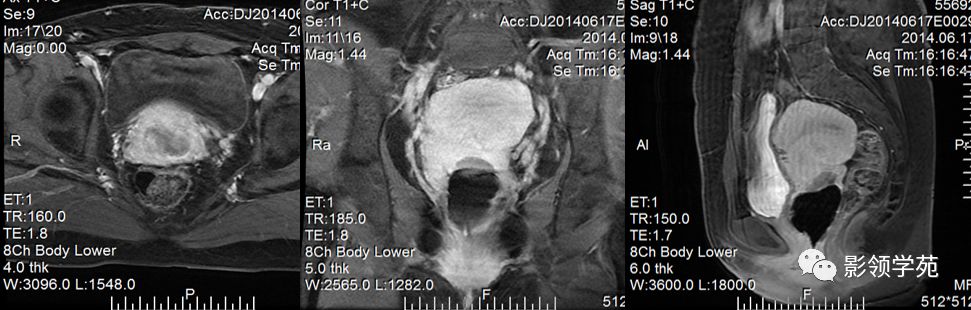

宫颈癌MRI表现

宫颈癌可表现为类圆形或不规则形肿块,在T2WI上表现为均匀或欠均匀的高信号,与正常宫颈基质及宫旁脂肪形成良好的自然对比。

MRI

- Ⅰ期肿瘤:侵犯宫颈基质,T2WI等信号肿块,宫颈管扩大及宫颈纤维基质中断

- Ⅱ期肿瘤:宫颈增大,宫旁肿块或宫旁脂肪组织内出现异常信号的粗线状影

- Ⅲ期肿瘤:侵犯至阴道下部,外延至盆壁,或出现肾积水。

- Ⅳ期肿瘤:膀胱壁或直肠壁低信号中断,膀胱壁或直肠壁增厚或腔内肿块。

DWI:局限性高信号,癌组织ADC值<癌旁组织<小于正常宫颈组织

Ⅰ期

IIA期

IIB期